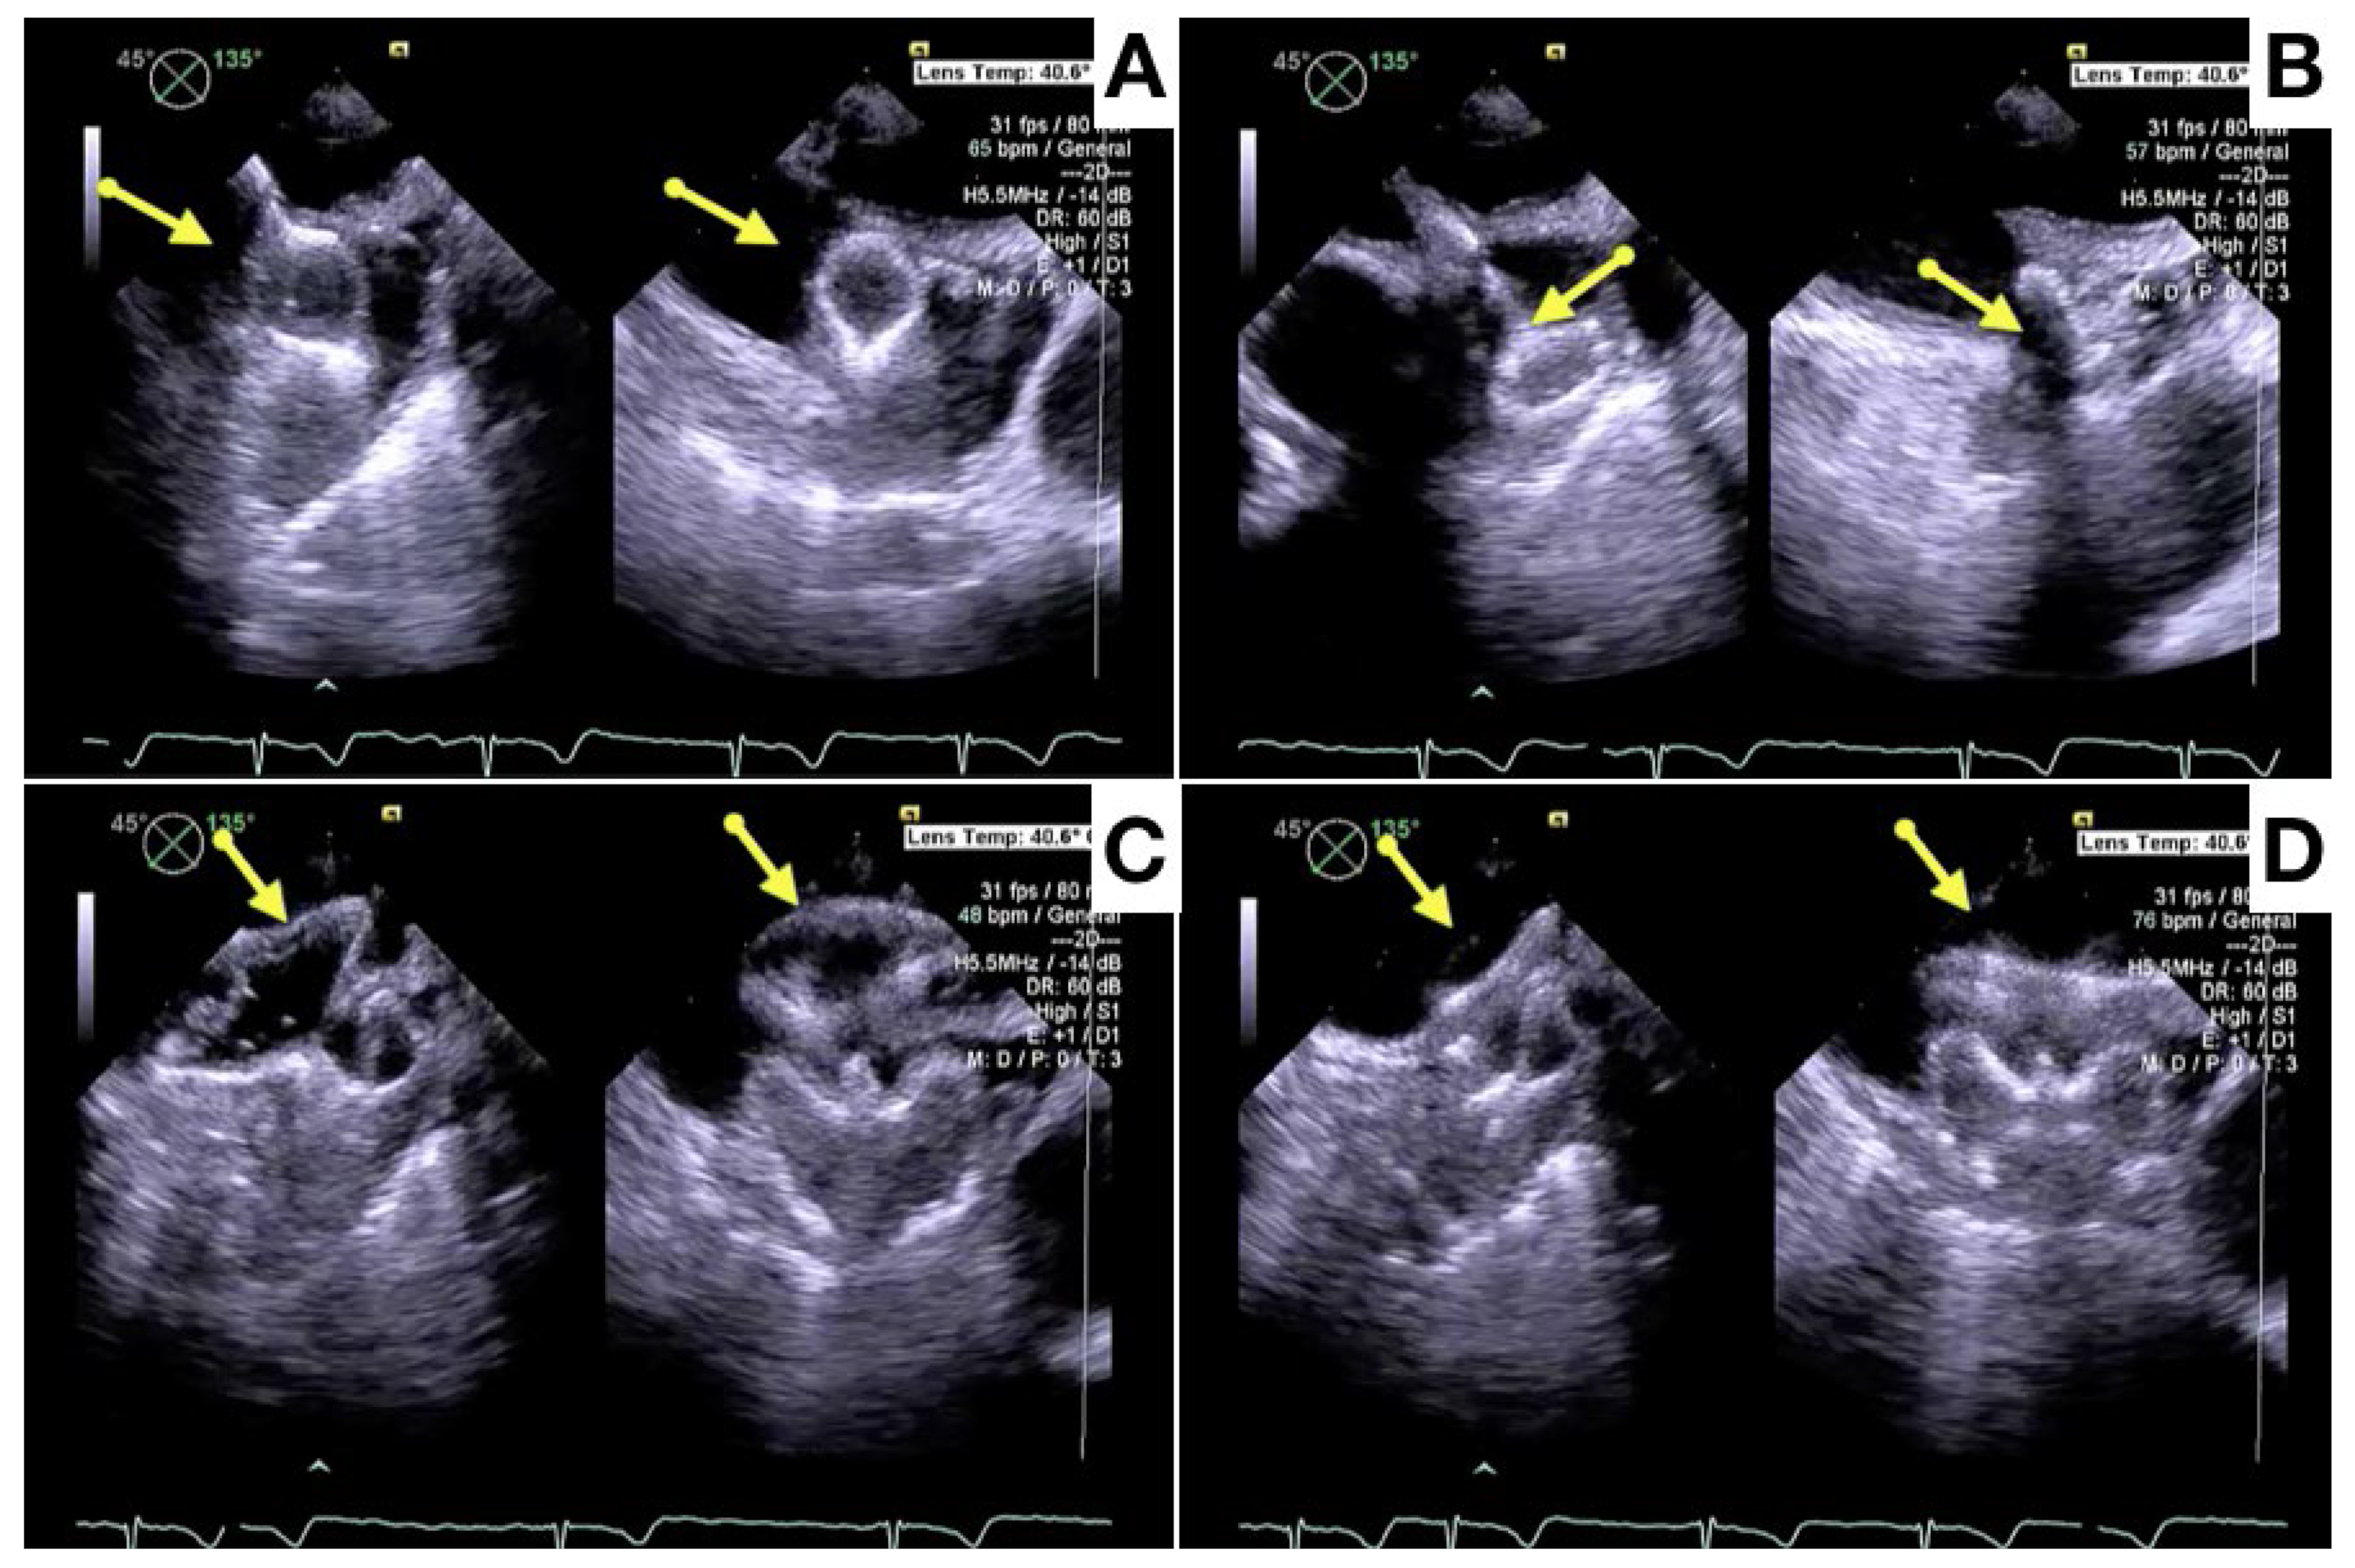

- Dukkipati, S.R.; Kar, S.; Holmes, D.R.; Doshi, S.K.; Swarup, V.; Gibson, D.N.; Maini, B.; Gordon, N.T.; Main, M.L.; Reddy, V.K. Device-related thrombus after left atrial appendage closure. Circulation 2018, 138, 874–885. [Google Scholar] [CrossRef] [PubMed]

- Alkhouli, M.; Busu, T.; Shah, K.; Osman, M.; Alqahtani, F.; Raybuck, B. Incidence and clinical impact of device-related thrombus following percutaneous left atrial appendage occlusion: A meta-analysis. J. Am. Coll. Cardiol. EP 2018, 4, 1629–1637. [Google Scholar] [CrossRef] [PubMed]

- Korsholm, K.; Jensen, J.M.; Nørgaard, B.L.; Nielsen-Kudsk, J.E. Detection of Device-Related Thrombosis Following Left Atrial Appendage Occlusion: A Comparison Between Cardiac Computed Tomography and Transesophageal Echocardiography. Circ. Cardiovasc. Interv. 2019, 12, e008112. [Google Scholar] [CrossRef] [PubMed]

- Simard, T.; Jung, R.G.; Lehenbauer, K.; Piayda, K.; Pracoń, R.; Jackson, G.G.; Flores-Umanzor, E.; Faroux, L.; Korsholm, K.; Chun, J.K.R.; et al. Predictors of Device-Related Thrombus Following Percutaneous Left Atrial Appendage Occlusion. J. Am. Coll. Cardiol. 2021, 78, 297–313. [Google Scholar] [CrossRef] [PubMed]